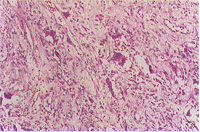

組織形態主要由纖維結締組織構成,排列成漩渦狀或輪輻狀,細胞之間為膠原纖維。不同病灶區內有不同數量的膠原纖維和纖維母細胞,這種梭形纖維母細胞被稱之為兼性纖維母細胞,病灶內還可見散在或成堆的多核巨細胞體積小,核一般為3~10個。也可見吞噬脂質和含鐵血黃素的組織細胞即泡沫細胞當大量泡沫細胞存在時,吞噬大量色素,標本呈銹棕色,易誤診為黃色瘤此外,還可見淋巴細胞和漿細胞分散於組織間,病變內無新生骨形成,周緣可見有反應性骨質硬化增生。

從組織學上還需要排除分化好的纖維肉瘤、骨巨細胞瘤,另外還與良性纖維組織細胞瘤相鑑別。從組織學上,有人認為這兩種組織學表現完全一致,但良性纖維組織細胞瘤多見於成年人,發病年齡偏大,除四肢骨外還可見於扁平骨,